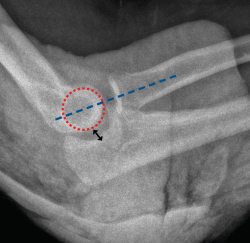

Figura 11. Radiografías de control en proyección anteroposterior y lateral en un paciente afecto de inestabilidad simple de codo persistente en el que se le realizó una reparación aguda del ligamento colateral lateral (LCL) y del ligamento colateral medial (LCM) mediante un sistema de arpones y suturas.

Típicamente, suele realizarse la reducción abierta mediante un abordaje posterior de codo o un abordaje lateral y medial combinado. En primer lugar, se aborda la zona lateral de la articulación del codo mediante un abordaje lateral de Kocher para realizar una inspección en busca de fragmentos óseos condrales o partes blandas interpuestas. El siguiente paso sería la reparación de LCL, el cual suele estar avulsionado de su inserción más proximal en el epicóndilo. La reparación típicamente se realiza mediante un sistema de anclaje con suturas, siendo importante también la posible lesión muscular de la región extensosupinadora. Una vez realizada la sutura de la zona ligamentosa y muscular lateral, se realiza una exploración bajo control escópico para evaluar la estabilidad del codo en rangos medios de movilidad y en posición de rotación neutra y pronación (evaluar la estabilidad del codo en supinación puede poner en riesgo la reparación del LCL). Si el codo sigue siendo inestable, entonces debe tenerse en cuenta realizar una reparación del LCM (Figura 10). Al igual que sucede con el LCL, la lesión del LCM suele localizarse en su inserción más proximal, aunque en ocasiones puede estar avulsionado del tubérculo sublime. La técnica de reparación empleada también suele ser mediante un sistema de arpón con suturas y, tras la realización de esta, deben repararse las lesiones asociadas en la musculatura flexopronadora (Figura 11). Si tras la reparación del LCL y del LCM, el codo sigue siendo inestable, debe colocarse un fijador externo de codo durante unas 4-6 semanas. Puede usarse, en función de las preferencias del cirujano, un fijador externo fijo o articulado.